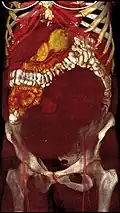

MRI image with multiple uterine leiomyomas -

Giant leiomyomas almost filling the abdomen -